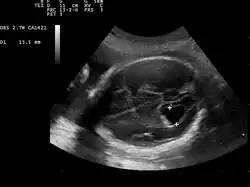

Ventriculomegaly

Ventriculomegaly is a brain condition that mainly occurs in the fetus when the lateral ventricles become dilated. The most common definition uses a width of the atrium of the lateral ventricle of greater than 10 mm.[1] This occurs in around 1% of pregnancies.[2] When this measurement is between 10 and 15 mm, the ventriculomegaly may be described as mild to moderate. When the measurement is greater than 15mm, the ventriculomegaly may be classified as more severe.[3]

This diagnosis is generally found in routine fetal anomaly scans at 18–22 weeks gestation. It is one of the more common abnormal brain findings on prenatal ultrasound, occurring in around 1–2 per 1,000 pregnancies.[4] In many cases of mild ventriculomegaly, however, there is resolution of ventriculomegaly during the pregnancy.